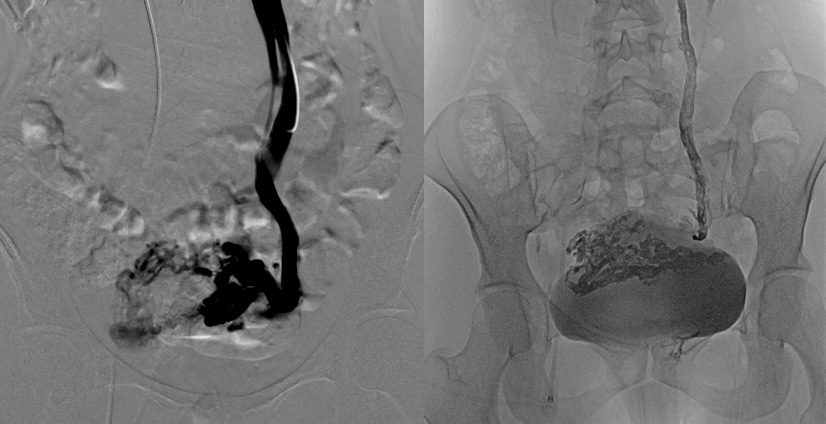

Phlébographie de la veine ovarienne gauche – Embolisation à la colle biologique

3. Phlébographie : une injection de produit de contraste iodé (comme pour un scanner) est utilisée pour réaliser une cartographie précise.

4. Embolisation : Une fois que le cathéter est placé au bon endroit, le matériel d'embolisation est injecté dans les veines afin de les obstruer et de stopper le flux sanguin (colle biologique ou sclérosant).